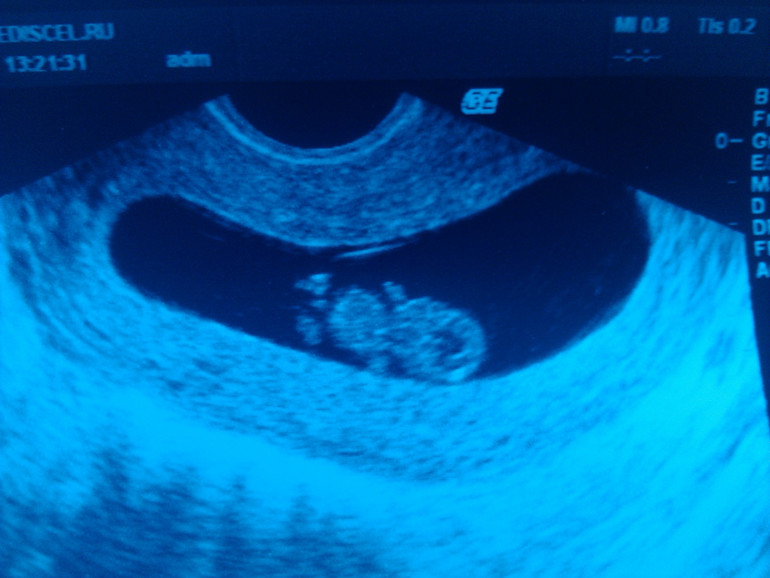

Были сегодня с будущим папой на УЗИ. Ходила провериться после перелета.

Мы уже большие и серьезные, в нас 22 мм, от макушки до попы. У нас есть голова, большая еще такая. У нас есть пузень, две ручки. На каждой ручке по пять пальчиков, мы пересчитали (выглядят, как точки, на фото, увы, уже не видно). У нас есть две ножки и пуповина. Есть даже желточный мешочек - пока он еще не рассосался, но мы его деловито выдвинули за пузырь) Сердечко бьется, 172 удара в секунду.

Ииииии самое главное! Мы шевелимся! Мы подергали ножками, пошевелились целиком, аж пузико заходило, а потом помахали папе ручкой! Я думала, Серега заплачет) Глаза были на мокром месте) После приема звонил свекрови и минут 10 ей рассказывал, эмоционально и возбужденно) Я давно не видела мужа таким счастливым)

По сроку соответствуем день в день)